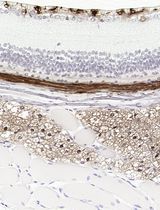

采用 Davidson 固定液和黑色素漂白法优化小鼠眼组织切片的免疫组化染色

Detection of senescent cells using a cytochemical assay was first described in 1995 (Dimri et al., 1995). The identification of senescent cells is based on an increased level of lysosomal β-galactosidase activity (Kurz et al., 2000). Cells under normal growth condition produce acid lysosomal β- galactosidase, which is localized in the lysosome. The enzymatic activity can be detected at the optimal pH 4.0, using the chromogenic substrate 5-bromo-4-chloro-3-indolyl β D-galactopyranoside (X-gal) (Miller, 1972). In comparison, upon senescence, the lysosomal mass is increased, leading to production of a higher level of β-galactosidase, termed senescence-associated β-galactosidase (SA-β-gal) (Kurz et al., 2000). The abundant senescence-associated enzyme is detectable over background despite the less favorable pH conditions (pH 6.0) (Dimri et al., 1995). The SA-β gal positive cells stain blue-green, which can be scored under bright-field microscopy. In this assay it is best to avoid over-confluency of the cells, or cells that have undergone too many passages, as these conditions can cause false positive results.